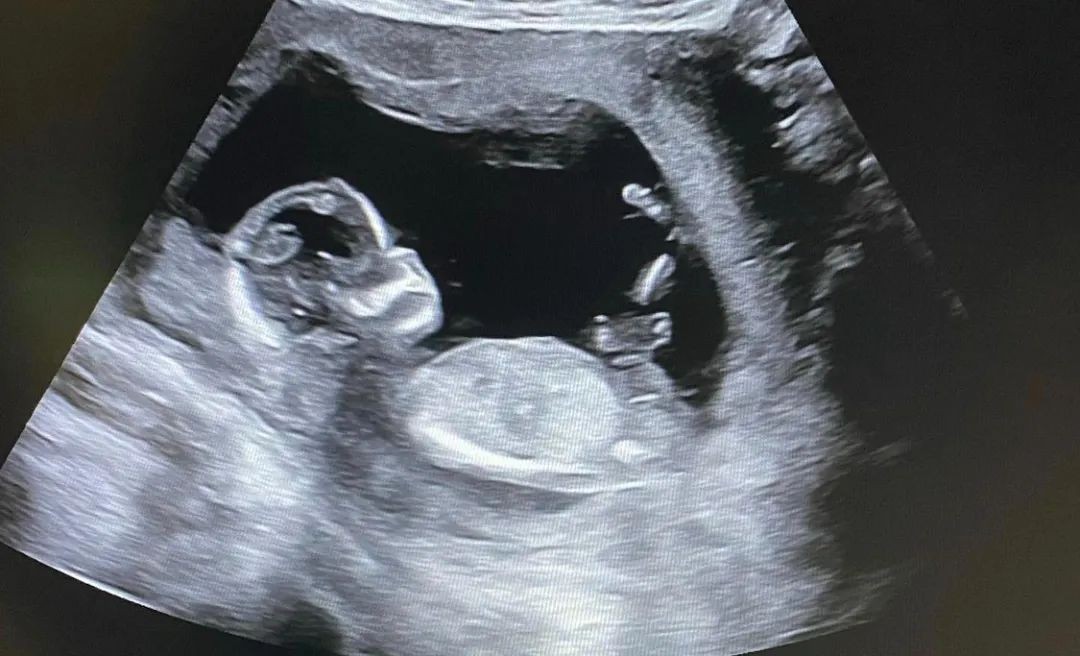

而且陈泰贤还将ins头像改为了胎儿B超的黑白照,同时个性签名中的“死产”一词也非常引人注目,可以感受到他的内心十分难受。